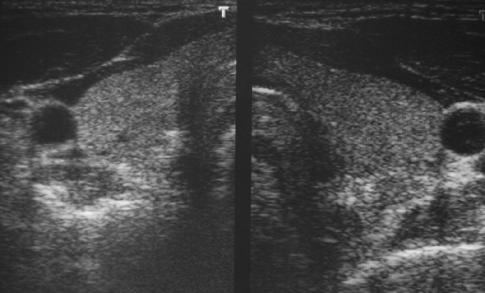

Schilddrüsensonografie

Die Schilddrüsensonografie ermöglicht

die Größenbestimmung der Schilddrüse.

Es lassen sich Schilddrüsenknoten und Zysten

(Flüssigkeitsblasen imGewebe) gut darstellen

Desweiteren kann die Strukturanalyse Hinweise auf

bestimmte Schilddrüsenerkankungen geben. z.B

auf einen M. Basedow.